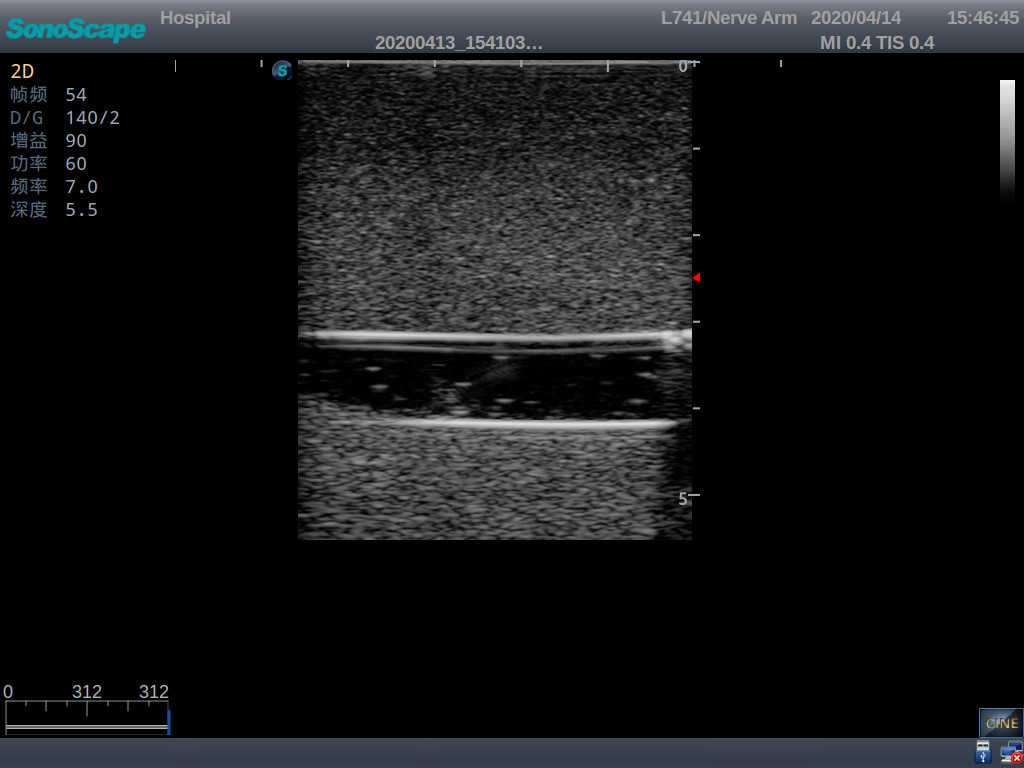

2)   It can be used by real ultrasound machines

3)   Clear and real images of the tissues and organs (basilic vein and superior vena cava)

5)   Observe the guide wire marches

6)   Detect whether the catheter is properly placed